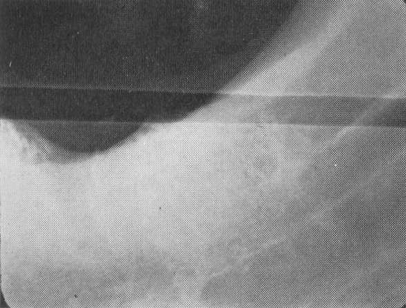

Roller or developer error